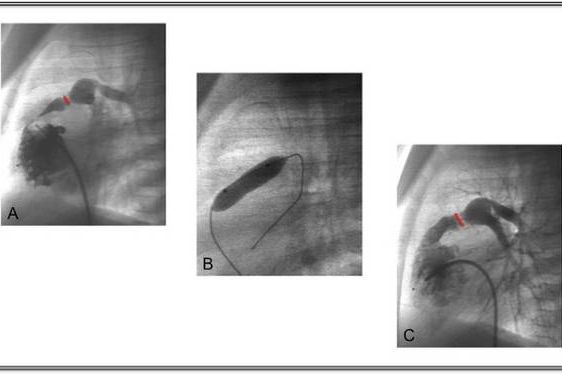

Dilatation of a pulmonary valve stenosis

A Illustration of the severe narrowing of the pulmonary valve (red marker),

B Position of the balloon in the valve,

C Result of the dilation with the valve region now clearly widened.